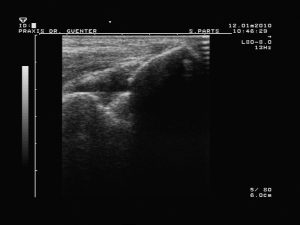

Abb.10 Sonogramm des Ellenbogengelenkes längs dorsal

Die Sonographie zeigt einen echoarmem Raum innerhalb eines Gelenkes (Abb.9 und 10) bzw. um eine Sehne (Spiegelei-Phänomen).